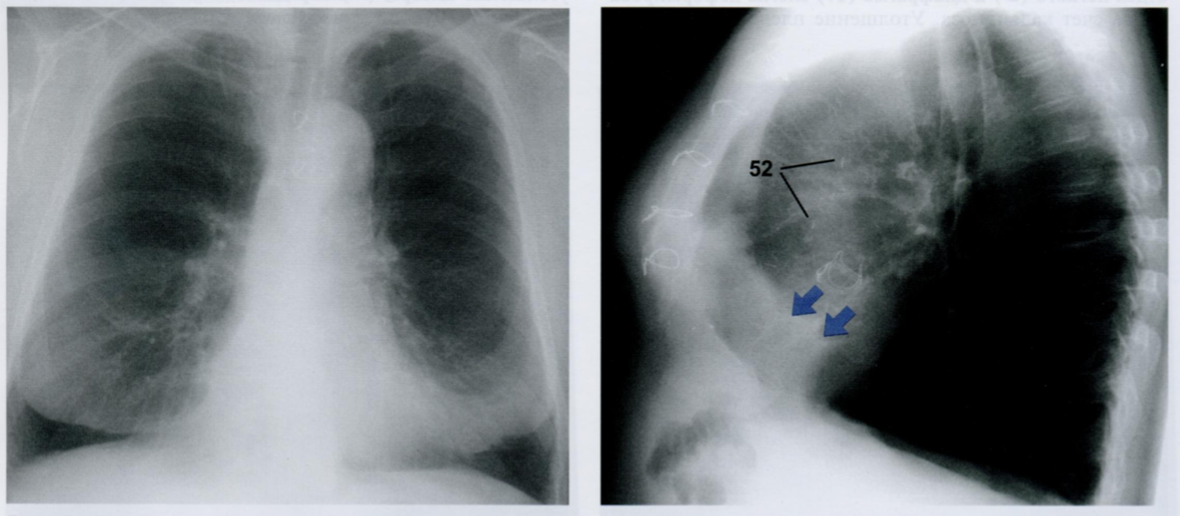

Оцените снимки.

На этом снимке довольно сложно разглядеть хирургические клипсы (52).

Фиброз плевры может развиться вследствие воспалительных изменений плевры или выпота в плевральную полость и чаще поражает висцеральный листок. Он представляет собой грануляционную ткань, которая может вторично обызвествляться. Первичный плевральный фиброз не имеет большого значения.

На снимках, особенно на боковой проекции (стрелки), заметны переднебазальные фиброзные наложения. В 3ПП они скрыты тенью сердца .

В этом случае фиброзные наложения являются следствием воспалительных изменений, развившихся после операции аортокоронарного шунтирования и протезирования клапана.